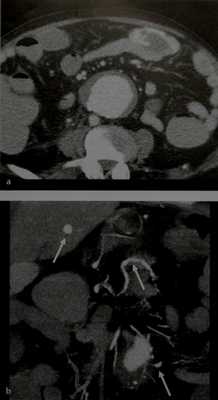

Острое артериальное кровотечение из псевдоаневризмы. Мужчине 43 лет по поводу РРЖ проведена химиотерапия, а затем тотальная резекция желудка (стадия T3N1). На 20-й день после операции больной доставлен скорой помощью в больницу с жалобами на боли в эпигастрии.

(а, б) При КТ без контрастирования выявлена гиперденсивная крупная гематома (указатели) в околоселезеночном пространстве и полости малого таза, имеется уровень жидкости и продуктов распада. Пунктирная стрелка указывает на ЭЕ-анастомоз.

(в, г) При КТ в артериальную (в) и отсроченную венозную (г) фазы контрастирования установлено фокальное накапливающее контраст узелковое образование (стрелка), расположенное вблизи металлического шовного материала ЭЕ-анастомоза (указатель) и примыкающее к левой ножке диафрагмы. Причиной рентгенологически подтвержденного гемоперитонеума могло стать кровотечение из псевдоаневризмы левой нижней диафрагмальной артерии (ЛНДА). Была предпринята попытка терапевтической эмболизации, однако технически это оказалось невозможным из-за ригидной ангуляции корня ЛНДА. После стабилизации состояния пациента проводили и медикаментозное лечение.

(д-з) Через две недели возник рецидив эпигастральных болей и развилась артериальная гипотензия. Проведена КТ-ангиография. При КТ-ангиографии в артериальную фазу (д), отсроченную венозную фазу (е), с помощью мультипланарной реконструкции в коронарной проекции (ж), а также с помощью метода объемного представления (з) выявлено увеличение размера псевдоаневризмы (стрелки), которая оказалась отдельной структурой, расположенной вблизи дилатированной селезеночной артерии (указатель). (продолжение) (и) Предпринята повторная ангиоинтервенция. В итоге после нескольких неудачных попыток выделения ЛНДА была успешно выполнена эмболизация псевдоаневризмы (стрелка) спиралями.

(к) Ангиография чревного ствола, выполненная после эмболизации, подтвердила, что псевдоаневризма больше не визуализирована (пунктирная стрелка). Гемоперитонеум, обусловленный кровотечением из культи короткой артерий желудка.